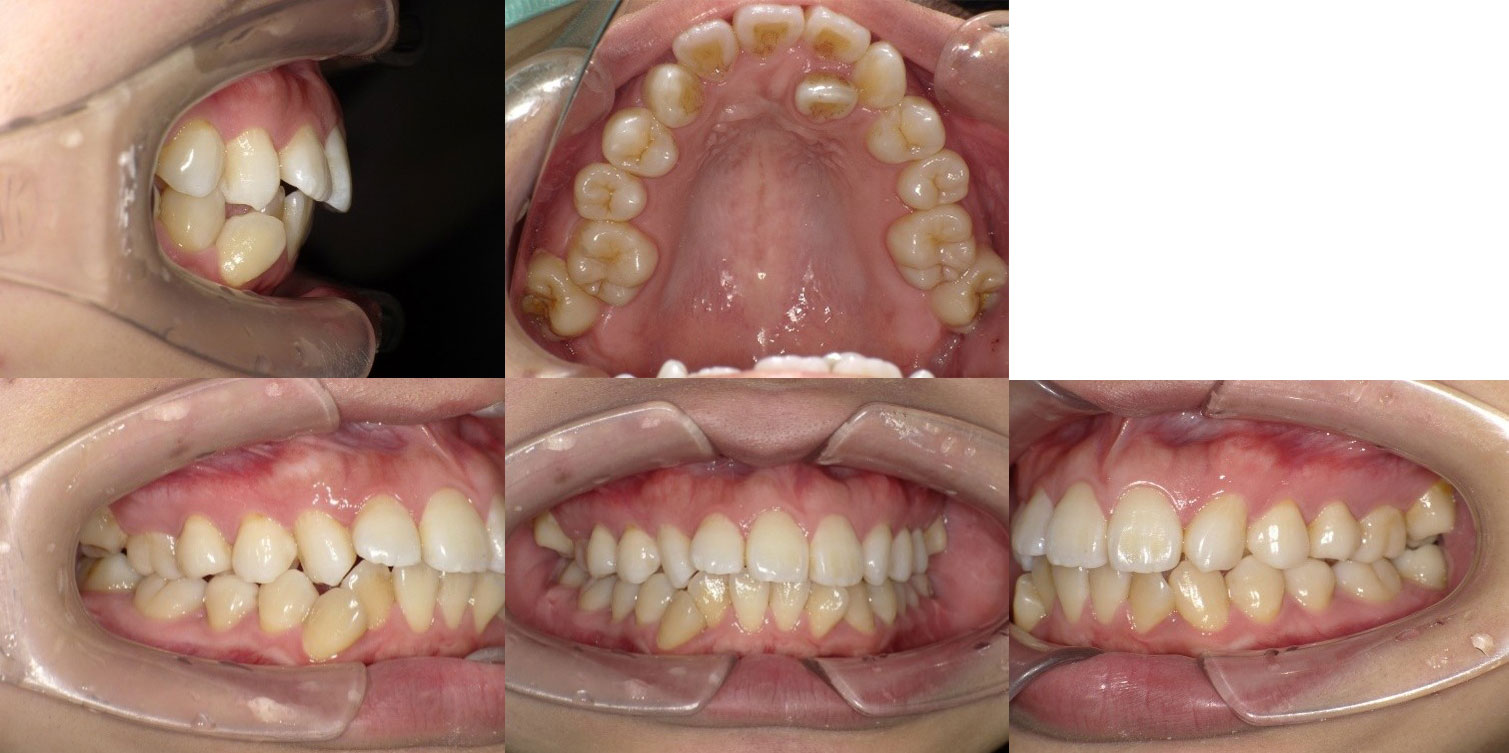

Before

患者様 27歳 女性

※矯正治療開始時

患者様のお悩み(主訴) ・歯並びが悪い(見た目)

・矯正専門医を受診したところ、小臼歯抜歯が必要といわれている

診断 ClassⅡ HighAngle 叢生 顎変位

顎関節に機能として問題あり

左右の動きに差がある

開口量が少ない

全体の歯並びも決して良くないのですが、患者様の一番気にされていたポイントとして上顎左側側切歯(一番前の歯の左隣の歯)が完全に内側に入ってしまってスペースが全くないという点でした。

矯正歯科では第一小臼歯を抜いてスペースを作ったり、内側に入っている側切歯自体を抜歯して並べたりする治療を提案されたそうです。